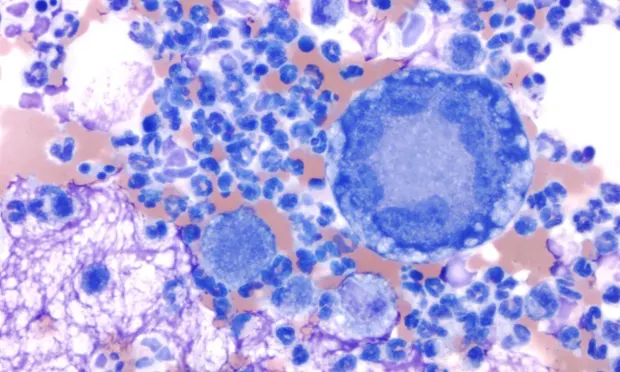

Cytologic evaluation. Smears were highly cellular and contained many inflammatory cells (Figure 1), moderate numbers of erythrocytes, and occasional clusters of columnar epithelial cells (Figure 2) in a thick background of mucus. The inflammatory cells were primarily neutrophils with moderate numbers of macrophages and relatively few multinucleated giant cells, lymphocytes, and plasma cells.

The epithelial cells were well-differentiated. Occasional extracellular yeast organisms (Figure 3) were identified. These organisms were round and 10 to 20 µm in diameter with a thick, blue wall and granular blue internal contents. Broad-based budding was common. No other etiologic agents were observed.

• Tracheal washes from healthy dogs typically have low cellularity and contain primarily ciliated and nonciliated columnar to cuboidal epithelial cells, macrophages, and a small amount of mucus. Neutrophils usually comprise less than 5% of the nucleated cell population. Other cells found in low numbers include lymphocytes (< 15%), eosinophils (< 5%), and mast cells (< 2%).3 Direct and concentrated smears of the fluid should be made as soon as possible after collection because cells deteriorate in vitro.• Pyogranulomatous inflammation occurs with fungal infections (e.g., blastomycosis, coccidioidomycosis, aspergillosis, histoplasmosis), protozoal infections, or foreign body reactions.3 Mixed inflammatory reactions are also found with necrosis associated with neoplasia or lung torsion.• The distinguishing cytologic features of the yeast form of Blastomyces dermatitidis are the round shape; size (generally 5 to 20 µm); thick, biconcave wall; granular internal contents; and frequent broad-based budding.3 The organism stains a dark blue with Romanowsky-type stains (e.g., Wright's stain, Diff-Quik). Hyphal forms are rarely found in tissues.1